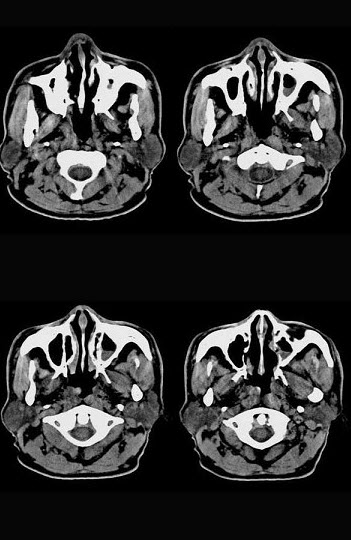

男,61岁,流鼻血三天。如图所示最可能的诊断为()。

A、鼻咽淋巴滤泡增生

B、鼻咽腺样体增生

C、鼻咽纤维血管瘤

D、小唾液腺瘤

E、鼻咽部息肉

正确答案:

A